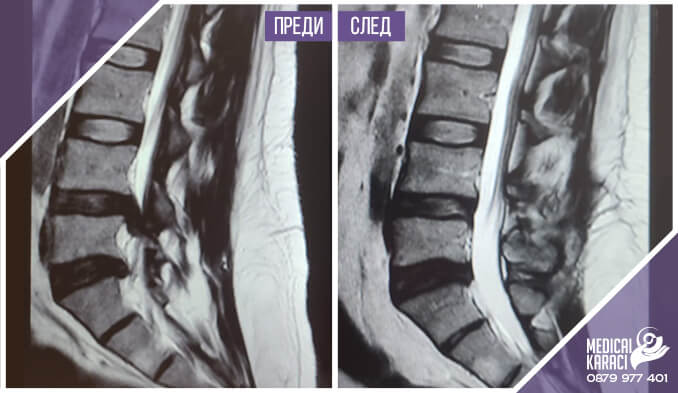

Free consultations with orthopedist Dr. Cengiz Çabukoğlu in Sofia on September 2nd and 3rd 2022